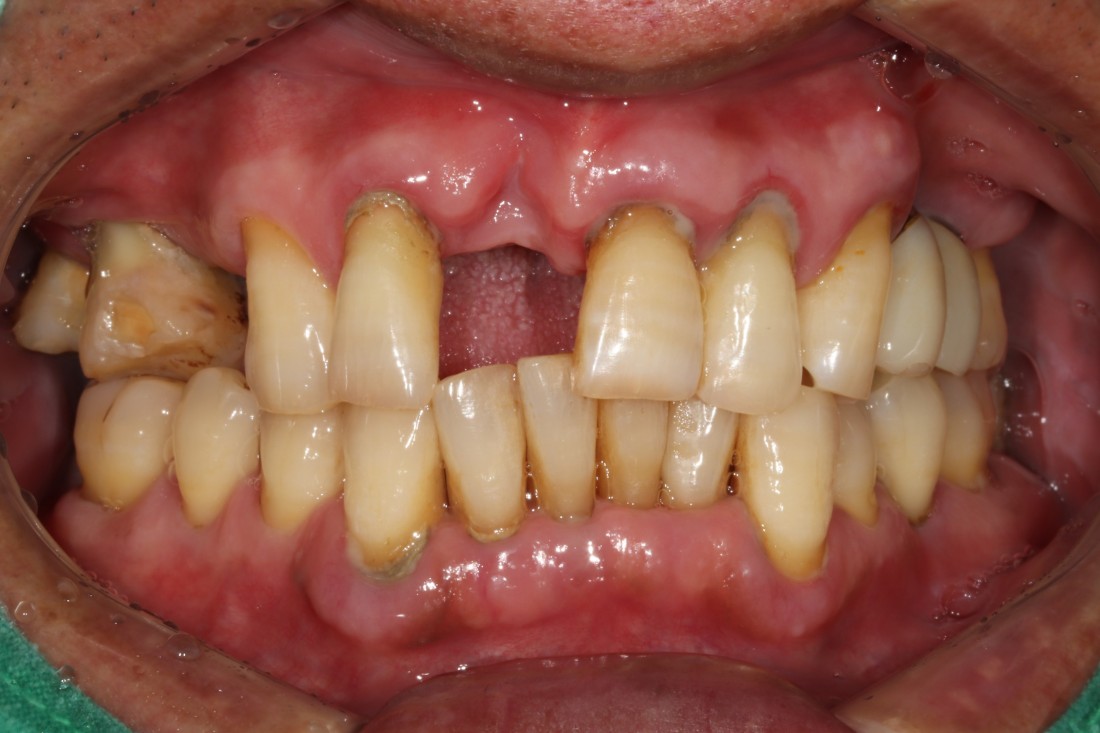

신경쓰이는 앞니 임플란트를

예쁘게 완성하는

광주 앞니임플란트 치과에서

광주 앞니임플란트가 필요할 때

무엇보다도 주변 치아와

잘 어울리고, 잘 씹어지는지가

앞니임플란트 성공의 포인트인데요.